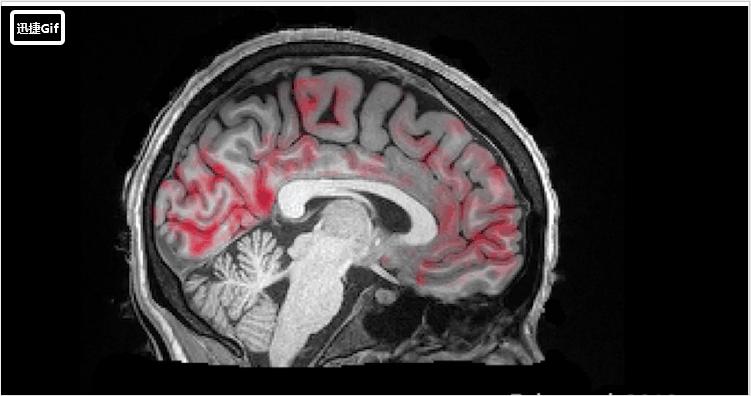

睡眠与阿尔茨海默氏病的病理之间的关系

科学家还观察到,睡眠改变与经过生物学标志或尸检得到的阿尔茨海默氏病病理学改变之间存在明确的联系。

比如,有的研究发现,在认知能力正常的中老年人,脑脊液中Aβ42蛋白水平低(代表阿尔茨海默氏病标志性淀粉样变Aβ蛋白高)的人睡眠效率较差;同时,睡眠质量差的人,脑内病理性蛋白水平就高。

如上所述,已经有研究证明,深睡眠会增加大脑对Aβ的清除,因此睡眠缺失就会反过来增强Aβ在脑内的集聚。